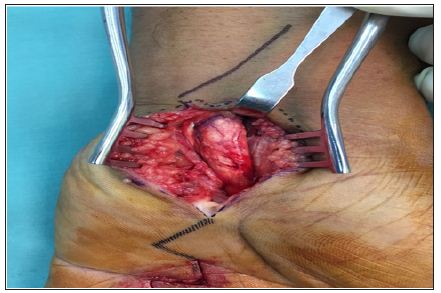

A 37-year-old male presented to our orthopaedic clinic with inability to extend his left ring finger. He previously diagnosed with left trigger ring finger and had surgical treatment to relieve the symptoms at another hospital centre 8 months before coming to our hospital. Post-operatively he was still unable to extend his finger (Figure 1). On physical examination, there was a swelling of 2x2cm found over the volar aspect of the forearm just proximal to the flexor retinaculum when the patient flexes his fingers. However on finger extension, the mass disappears. Due to prolong inability to extend his left ring finger he had developed a flexion contracture. Our working diagnosis was incomplete released of left 4th finger A1 pulley, TB tenosynovitis, followed by soft tissue neoplasmand subsequently surgical exploration was performed. We proceed with surgical exploration over the previous surgical scar over the A1 pulley of left ring finger. We noted that the A1 pulley has been completely released. However his finger was still in the flexed position. We decided to do an extended carpal tunnel incision to explore the mass proximal to flexor retinaculum. We noted whitish chalky infiltration of the Flexor Digitorum Superficialis (FDS) tendon, synovial adhesion to other tendons and hypertrophy of the flexor tendon (Figure 2 & 3). Synovectomy and excision of the chalky infiltration of the FDS tendon was performed. Histo-pathological evaluation confirmed the diagnosis of gout. Post-operatively, patient was able to extend his left ring finger but with some degree of stiffness but after 2 months of intensive physiotherapy he regained full range of movement to that finger.

Figure 2: Classical carpal tunnel release done-noted whitish chalky infiltration of the tendon of the FDS, synovial adhesion to other tendons and hypertrophy of the flexor tendon.

Figure 3:The arrow shows tophaceous gout in the FDP of the left ring finger.